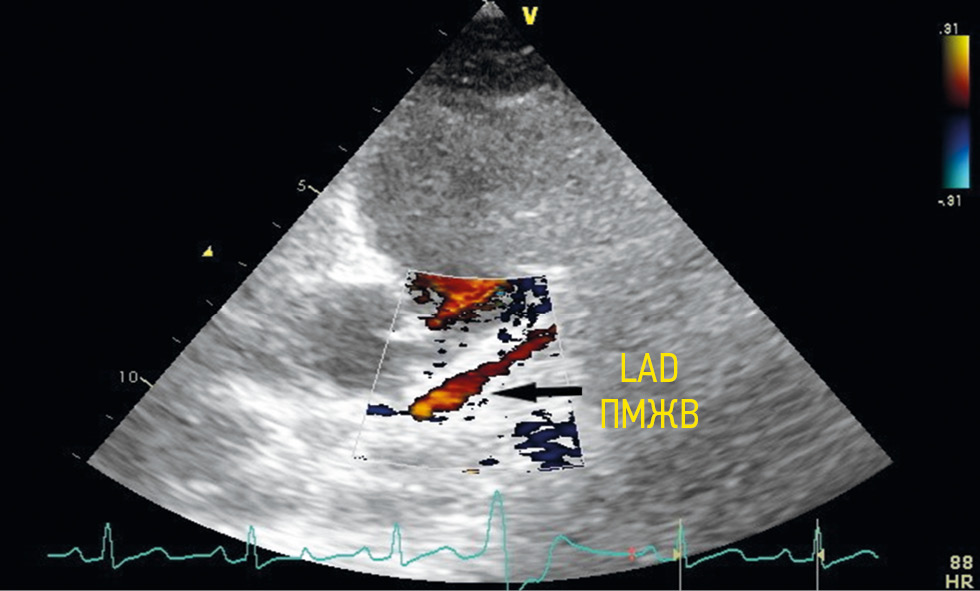

The left anterior descending (LAD) artery was visualized based on the following anatomical features: the anterior interventricular sulcus, the initial origin of the first diagonal artery, and the papillary muscles. A normal antegrade red blood flow was determined by color Doppler imaging. The proximal segment of the LAD was visualized by slightly changing the image plane in the modified left parasternal position along the short or long axis (Figure 2).

Fig. 2. Visualization of the anterior interventricular branch from a modified left parasternal position. LAD — left anterior descending artery / Рис. 2. Визуализация передней межжелудочковой артерии из модифицированной левой парастернальной позиции. ПМЖА — передняя межжелудочковая артерия

The midline LAD segment was visualized from the third or fifth intercostal space in the inferior left parasternal and the modified parasternal positions along the short or long axis of the left ventricle in the anterior interventricular sulcus and the modified apical tricuspid position (Figure 3).

Fig. 3. Visualization of the anterior interventricular branch middle segment from a modified short-axis parasternal position in the anterior interventricular sulcus. LAD — left anterior descending artery / Рис. 3. Визуализация срединного сегмента передней межжелудочковой артерии из модифицированной парастернальной позиции по короткой оси в передней межжелудочковой борозде. ПМЖА — передняя межжелудочковая артерия